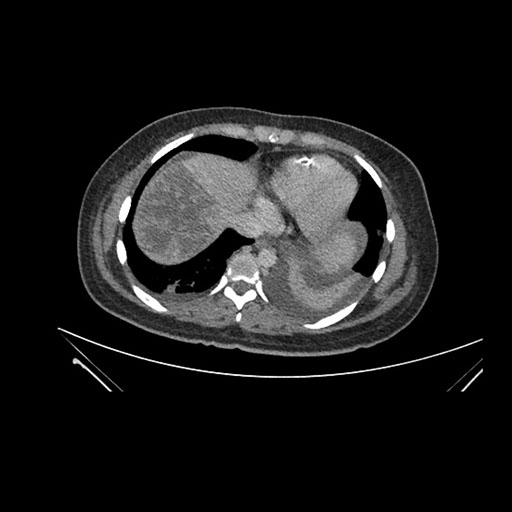

Axial Arterial

Imaging analysis

Based on initial findings, which issue(s) would you be most concerned about?